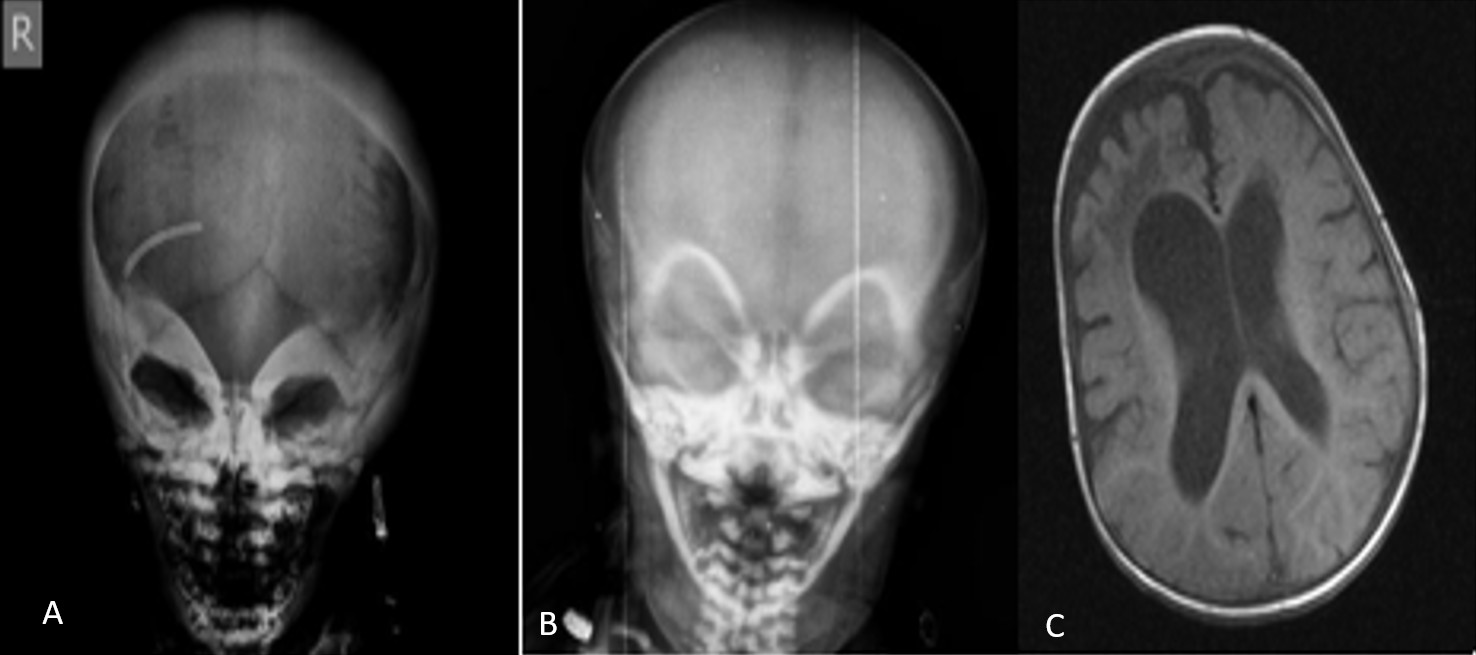

A total of 12 patients (7 female, 5 male) from ten distinct families were included. All patients were born to consanguineous parents. The median age at diagnosis was three months (range, 1 to 36.5 months). The most common presenting symptoms were nasal congestion and difficulty sucking (n=4) (Table 1). Radiographic assessments in all 12 patients revealed features typical of osteopetrosis, including diffuse bone sclerosis, thickened skull bones, a “sandwich vertebrae” appearance, and a “bone-within-bone” sign (Figure 1 and Figure 2).

This group included Patients 8, 9, and 10, all of whom carried the same homozygous splice site mutation in OSTM1. These patients presented with a severe neurodegenerative phenotype. All three exhibited neurodegenerative changes on cranial imaging, including diffuse cerebral atrophy and a thin corpus callosum, and had a history of seizures. Two patients died during the study period.

CLCN7-related osteopetrosis (n=2)

Patients 11 and 12 had homozygous missense mutations in CLCN7. Both patients presented with a severe phenotype that included neurodegenerative changes. Patient 11 had hydrocephalus and seizures, while Patient 12 had vision loss and hepatosplenomegaly. Both patients in this group died.